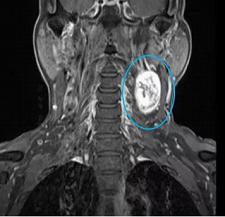

张先生和赵先生住院以后都做了颈部的磁共振检查,检查结果显示张先生的肿块长在了下颌角的边上,肿块还包绕着颈部的大血管。而赵先生的肿块是从臂丛神经上长出来的。

张先生颈部磁共振